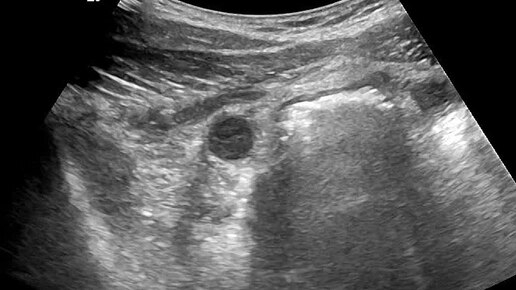

Ультразвуковые находки от врача УЗД Зорина Я.П.